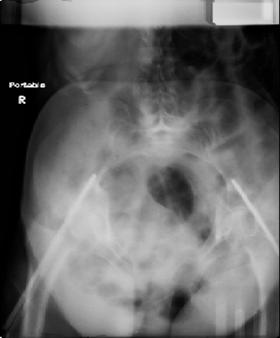

attached are images of a 70 year old female after peds versus car. her own car ran her over.

injuries are limited to the pelvis. left rami open and visible in a 10cm vertical laceration just lateral to left labia majora. wound is grossly clean. no vaginal and no urinary issues. CT scan shows widening of both SI joints anteriorly but I think this is vertically stable pattern.

pt treated that night with I/D and supra-acetabular frame to close the ring. consideration was given for SI screws bilateraly, but given time of night and other factors decision made not to proceed.

maintaining pelvic alignment in ex-fix in 70 yo female for any length of time may be challenging.

any thoughts? would anyone plate the pubic symphysis to close the gap and leave the more lateral rami fractures alone? the most recent pelvic case on this website involved pts with suprapubic catheters and antibiotic options including resorbable beads. I wonder how many people would plate and place antibiotic beads. thanks.